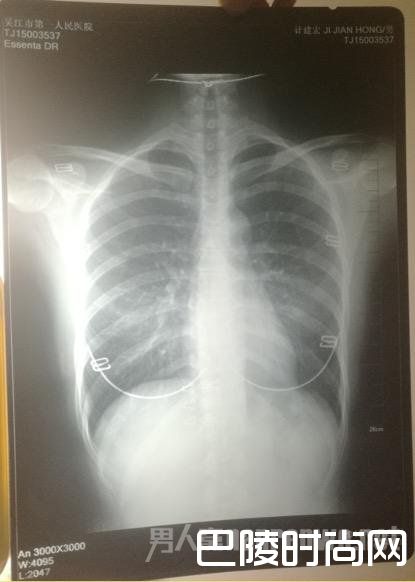

印着父亲姓名的胸片,图像却显示有明显女性文胸搭扣和项链的印记。

胸片

“当时我和母亲都奇怪,一年多前体检正常,怎么这么快肿瘤长得如此大了?”更令计云强疑惑的是,该院胸外科主任在系统中输入计建宏姓名后,查询得到的胸片,可明显看出有女性文胸的搭扣和项链,“后来医生含糊地说可能是同名同姓,便不让我看了。”

“7月初,我们回到吴江,带着满心悲伤和疑虑去了体检科,想搞清楚父亲的胸片究竟是怎么回事。”计云强称,此后几经周折,在找了吴江区第一人民医院体检科、投诉科等多个部门后,耗时多月,才被体检科通知去拿父亲的胸片,“一张是我父亲的名字,但有文胸印记;另一张是医院所谓的我父亲的胸片,显示的是其他人的姓名。”